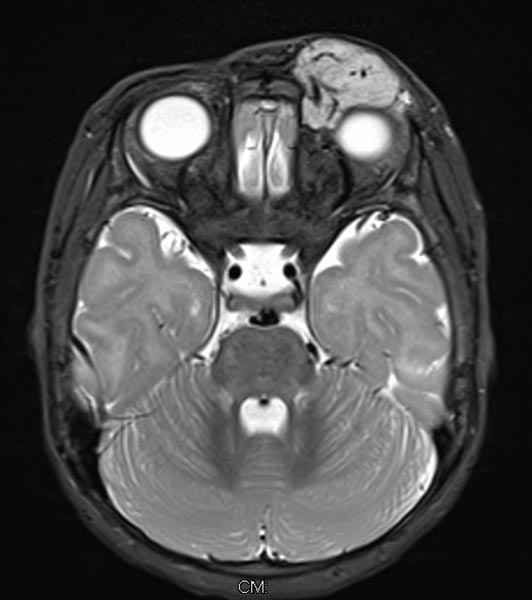

T2-gewichtete axiale MRT ohne Fettsättigung. Die Raumforderung medial am linken Auge ist auch hier relativ homogen hyperintens und zeigt zentrale flow-voids. Aufgrund der fehlenden Fettsättigung ist die Raumforderung aber nicht so gut vom umgebenden Fettgewebe abgrenzbar.